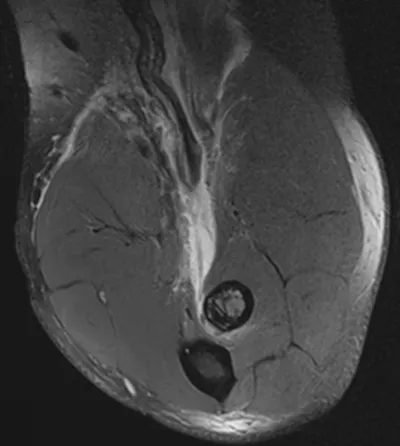

Synovial Osteochondromatosis of Elbow

Elbow

4/10/2026